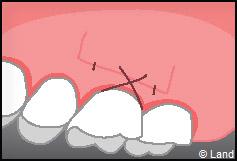

LES TECHNIQUES SANS APPORT DE GENCIVE :

Elles font appel à des lambeaux de gencive restante à proximité des récessions, qui sont déplacés et repositionnés sur la récession.